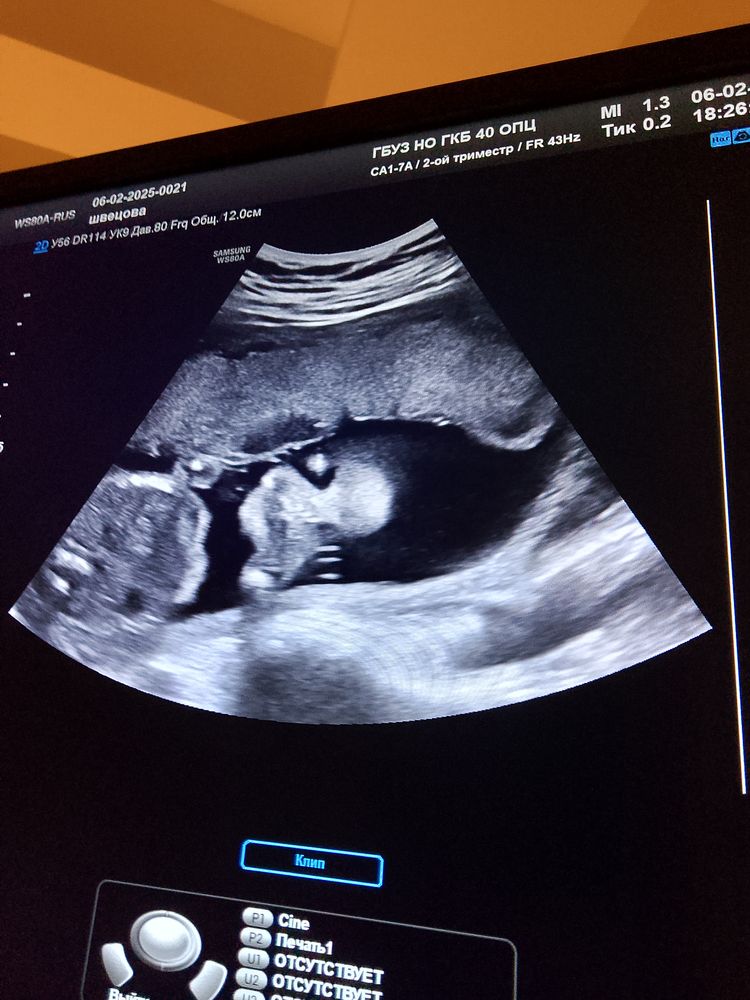

Masha в Благополучная беременность 10 месяцев Что изображено на снимках?) УЗИ, КТГ, доплер Кто разбирается в узи, подскажите, что тут🥰 Посмотрите еще 20 записей на эту тему Лучший ответ JuLi на первых двух голова(глазницы, лицо ) и пальчики, кусочек туловища, на третьей ступни и низ живота 06.02.2025 Ответить Отменить Ответить Светлана Лицо и кисть на 1-2))) криповенько вышло))) пятки и вид снизу на 3) 06.02.2025 Ответить Masha Светлана, 😁😁😁 06.02.2025 Ответить Mur mur Лицо с ручкой, машет 06.02.2025 Ответить Mur mur Лицо на первых двух, на нижнем стопы, все же понятно😅 06.02.2025 Ответить Яна Голова гуманоида 😂у нас еще веселее фото😂 07.02.2025 Ответить Утрожестан до 34 недели, шейка 28 см в 30 нед УЗИ Чаты Беременных Выберите чат: Январята-2026 Февралята-2026 Мартята-2026 Апрелята-2026 Майчата-2026 Июнята-2026 Июлята-2026 Августята-2026